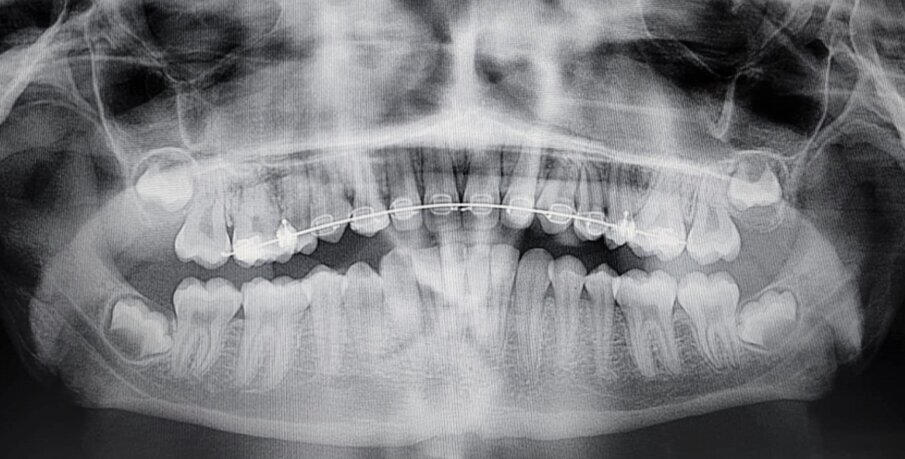

Figg. 2a, 2b: Rx-OPT iniziale di una paziente di anni dieci con trasposizione caninopremolare 1.3-1.4 e ritenzione canina dell’elemento 23(A); Rx-OPT in corso di trattamento della stessa paziente, in cui è mostrata la risoluzione ortodontica con mantenimento dei denti trasposti nel primo quadrante (B).